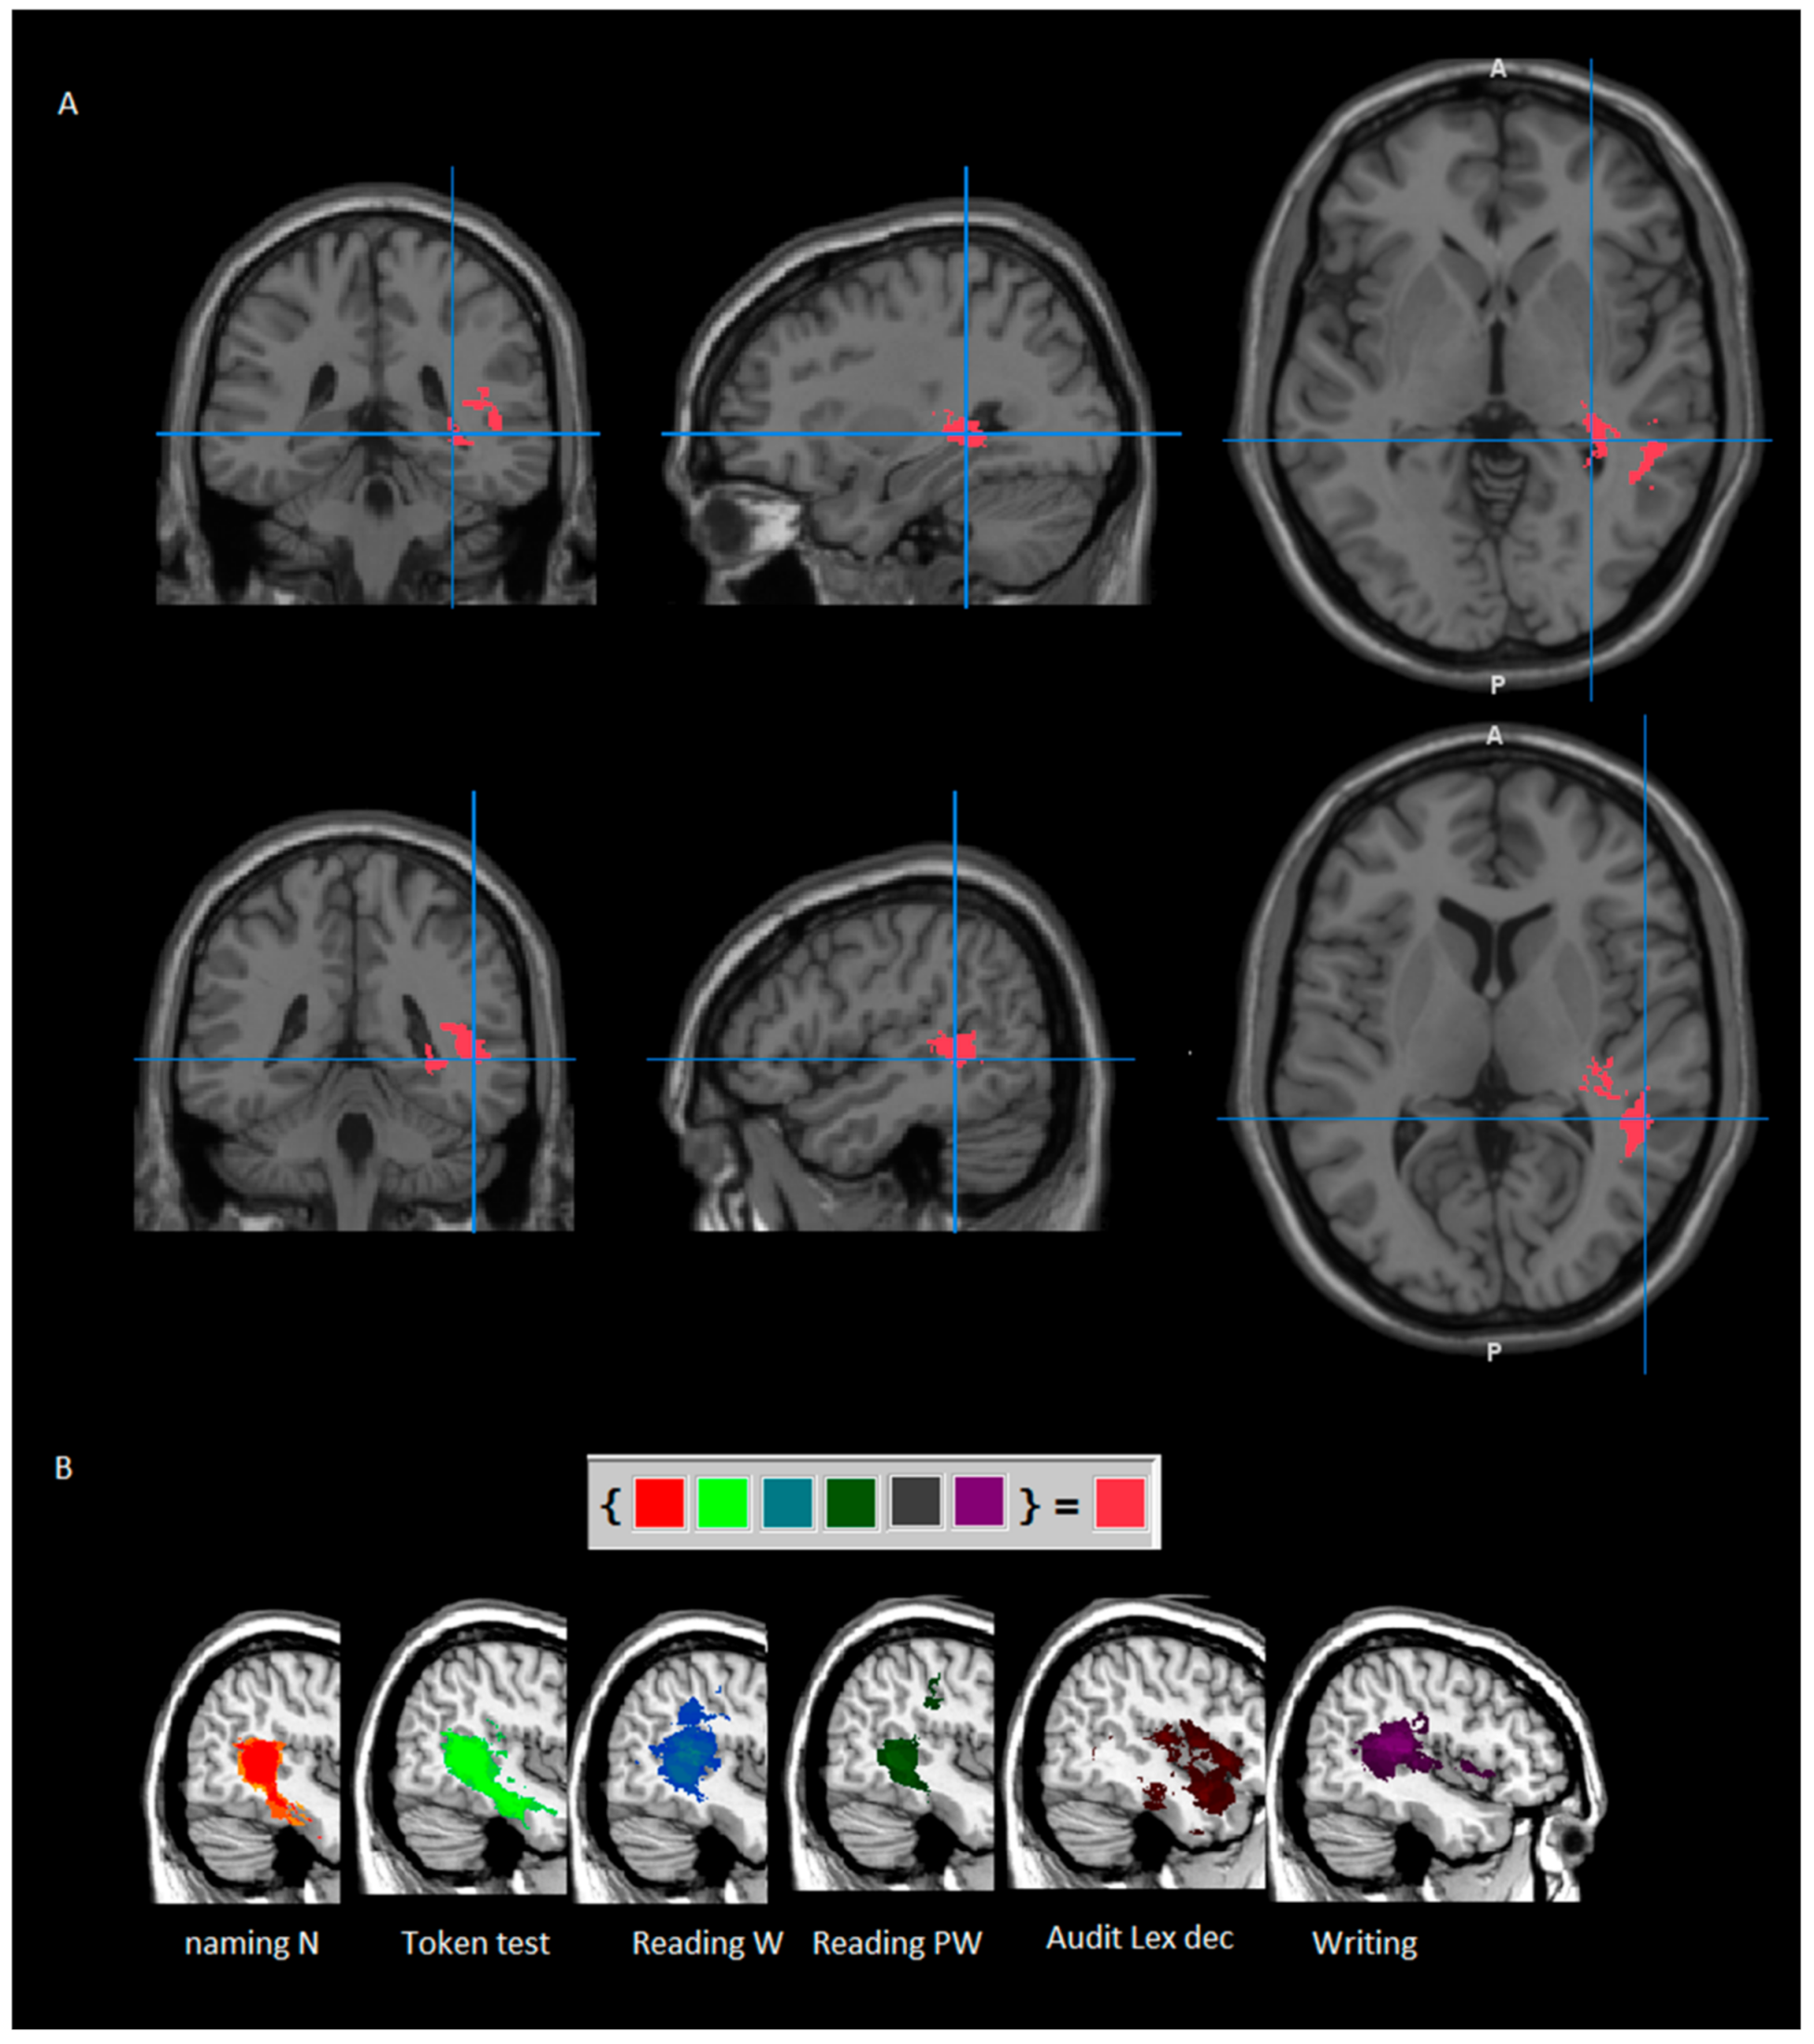

3.2.4. Further Investigations: Intersection Area

- Only tasks for which the maximum lesion overlap in the output image (lesion overlay of pathological patients—lesion overlay of spared patients) was at least >20% are reported (for a complete list of coordinates, see Supplementary Table S1). Local maxima (See Figure 2 and Table 5) were localized as follows:

- for verb naming: in the superior and middle temporal gyrus (25% and 24%);

- for phonological fluency: in the hippocampus (22%) and, at subcortical level, in the retrolenticular part of the internal capsule (26%);

- for short-term memory: in the superior temporal gyrus (30%), and, at subcortical level, in the retrolenticular part of the internal capsule (overlap: 26%) and sagittal stratum (including IFOF and ILF, 26%).

- for word reading, performed by 55/85 patients: in the superior temporal gyrus (57%) and, at subcortical level, in the superior longitudinal fasciculus (57%), the posterior thalamic radiation and the retrolenticular part of the internal capsule (47% and 44%) and the sagittal stratum (including IFOF and ILF, 36%);

- for pseudo-word reading, performed by 55/85 patients: in the calcarine cortex and the middle and inferior temporal gyrus (37%) and, at subcortical level, in the posterior thalamic radiation (39%), in the SLF (37%) and the retrolenticular part of the internal capsule and the tapetum (37%);

- for auditory lexical decision, performed by 41/85 patients: in the superior temporal gyrus (40%) and, at subcortical level, in the sagittal stratum (including IFOF and ILF, 36%);

- for writing, performed by 46/85 patients: in the superior temporal gyrus (58%) and, at subcortical level, in the SLF (45%).